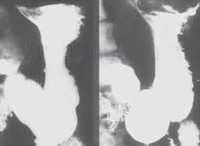

Рентгенография желудка. Это неинвазивный метод диагностики, используемый для выявления заболеваний желудка, пищевода и двенадцатиперстной кишки. С помощью этого исследования можно оценить состояние слизистых оболочек и мышечной сферы стенок этих органов, их форму и общий размер, структурные характеристики сердечного и пилорического сфинктеров. Рентгенография желудка информативна в диагностике гастрита, новообразований желудка, язвенной болезни желудка, стеноза, выпячивания, перфорации, послеоперационных состояний Как правило, рентгенография проводится как самостоятельная процедура, с контрастным улучшением или нативным. В качестве препарата может потребоваться голод до или промывание желудка.

Рентген желудка является диагностической процедурой, суть которой заключается в поглощении структурами тела лучей, испускаемых рентгеновской трубкой. Степень поглощения рентгеновских лучей варьируется в зависимости от плотности тканей. Устройство фиксирует прошедшее и поглощенное излучение, тем самым формируя изображение - рентгенограмму. Это явление впервые было описано немецким физиком Вильгельмом Конрадом Рентгеном в 1895 году. В настоящее время рентгенография желудка является наиболее распространенным неинвазивным методом диагностики заболеваний желудочно-кишечного тракта. Он относится к первой линии инструментальных исследований, позволяет подтвердить предварительный диагноз или определить будущий план обследования. Основными областями медицины, в которых используется эта техника, являются гастроэнтерология, онкология и хирургия.

По результатам рентгенологического исследования желудка оценивается структура стенок нижнего пищевода, сфинктера сердца, желудка, пилоруса и начальных отделов двенадцатиперстной кишки. Наличие язв, гастритов, протрузий, опухолей свидетельствует о дефектах стенок и их структурных изменениях. Когда стеноз значительно уменьшает просвет одного из отделов исследуемых органов, противоположные стенки примыкают друг к другу. Структурные нарушения мышц пищевода сфинктера указывают на наличие ГЭРБ.